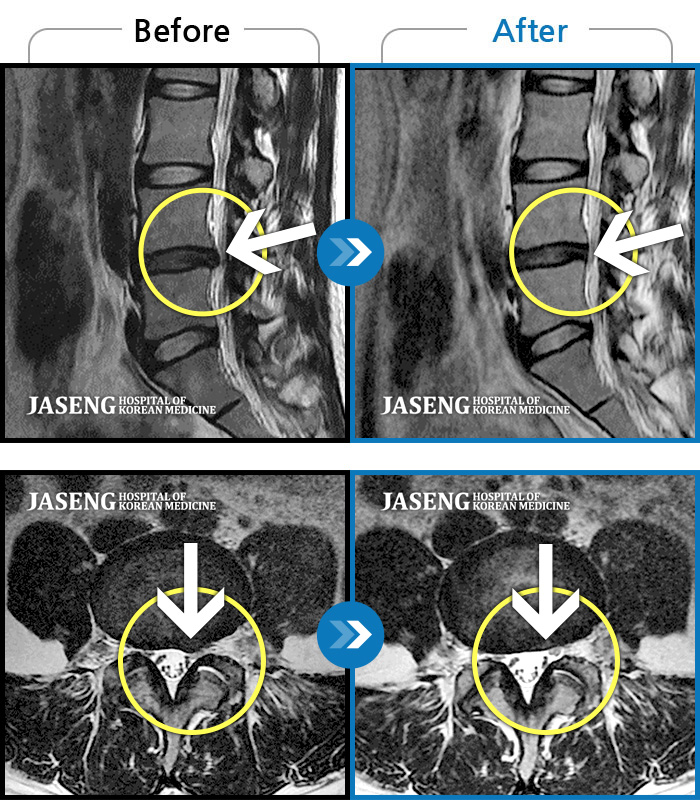

ȯںп Ǹ ǿ ԿǾ, ο ġ ۿ Ƿ ġḦ Ͻñ ٶϴ.